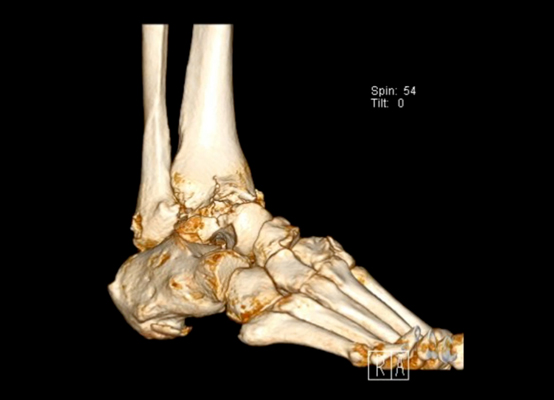

TOTAL ANKLE REPLACEMENT :: ORIF CALCANEUS :: ORIF ANKLE FRACTURE DISLOCATION :: COMPLEX BUNION AND LESSER TOE CORRECTION :: TALUS FRACTURE -1 :: TALUS FRACTURE -2 :: LISFRANC REPAIR :: COMPLEX TRIPLE ARTHRODESIS 1 :: COMPLEX TRIPLE ARTHRODESIS 2 :: MINIMALLY INVASIVE BUNION REPAIR 1 :: MINIMALLY INVASIVE BUNION REPAIR 2 :: ARTHROSCOPIC CARTILAGE REPAIR :: TENEX SPUR DEBRIDEMENT :: Haglunds Debridement and Achilles Repair